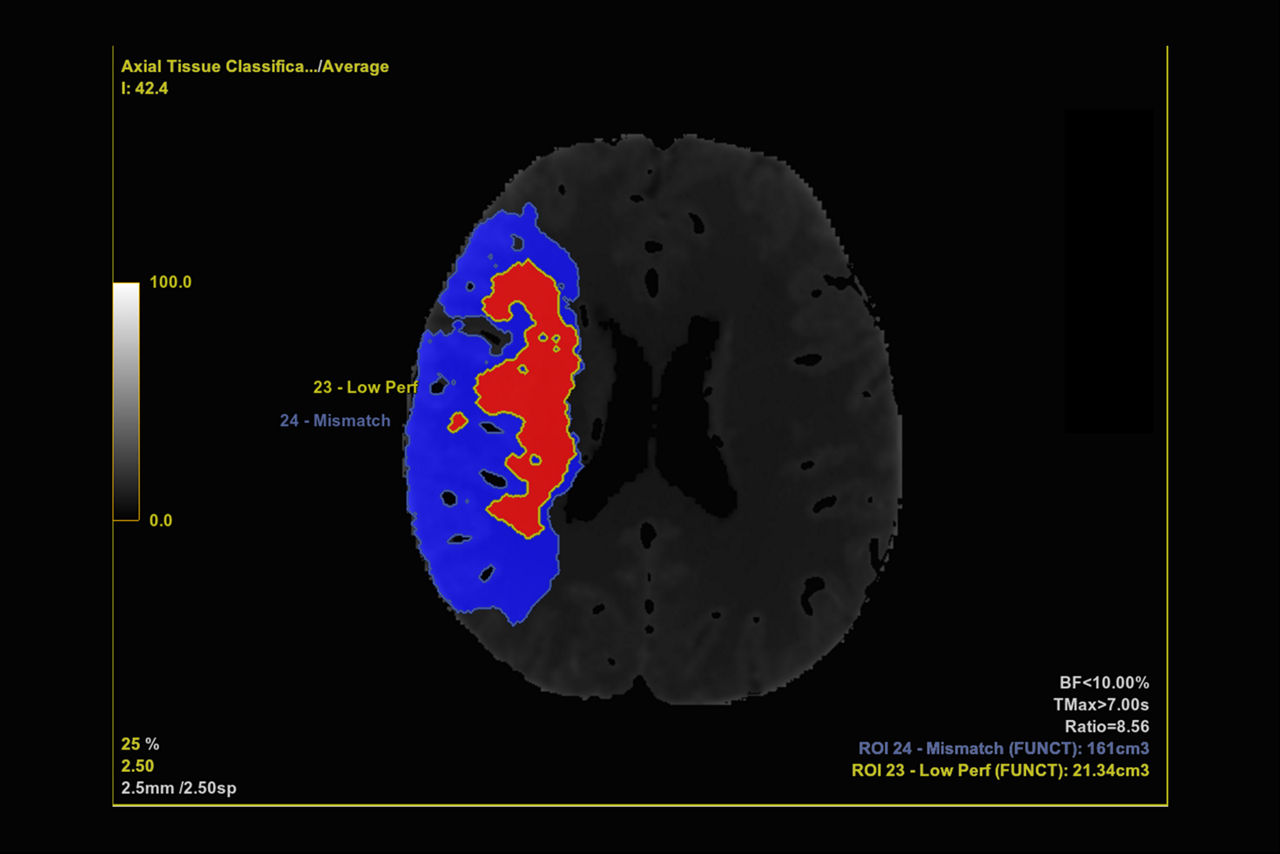

Brain stroke protocol

• Tissue Classification enables the visualization of regions that are segmented from absolute or relative values, customizable thresholds and user selectable input maps

• Mismatch volume and ratio are calculated from the modified perfusion volume and low perfusion volume ROIs